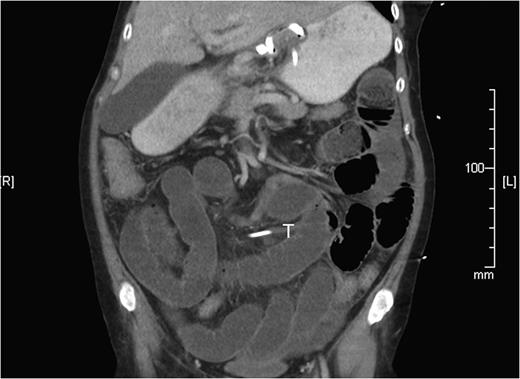

Two weeks later, she re-presented to the emergency department with a 24-hour history of severe central abdominal pain associated with vomiting and multiple episodes of loose stools. On examination, she was found to be hypotensive, tachycardic and peritonitic. The suspicion of an SBO was established by plain film radiograph appearances with multiple air fluid levels and distended bowel loops (Fig. 1). Computed tomography scan of the abdomen and pelvis showed the transitional zone to be in mid abdomen (Fig. 2). This was thought to be most likely secondary to adhesions. She proceeded on to have an emergency laparoscopy. Interestingly, the laparoscopy identified the transition point of the SBO to be an adhesion formed between the LAGB tube, the mid jejunum and the stomach forming a classic closed-loop obstruction (Fig. 3). The laparoscopic division of this adhesion was performed successfully. The rest of the small bowel was run along its entire length with no other transition point found. The adjustable gastric band was removed at the same time along with the associated port. Postoperatively, she had an uncomplicated recovery and was discharged on Day 4 post-admission without further sequelae.

SBO established on plain abdominal radiograph, with gastric band tubing and port also evident.